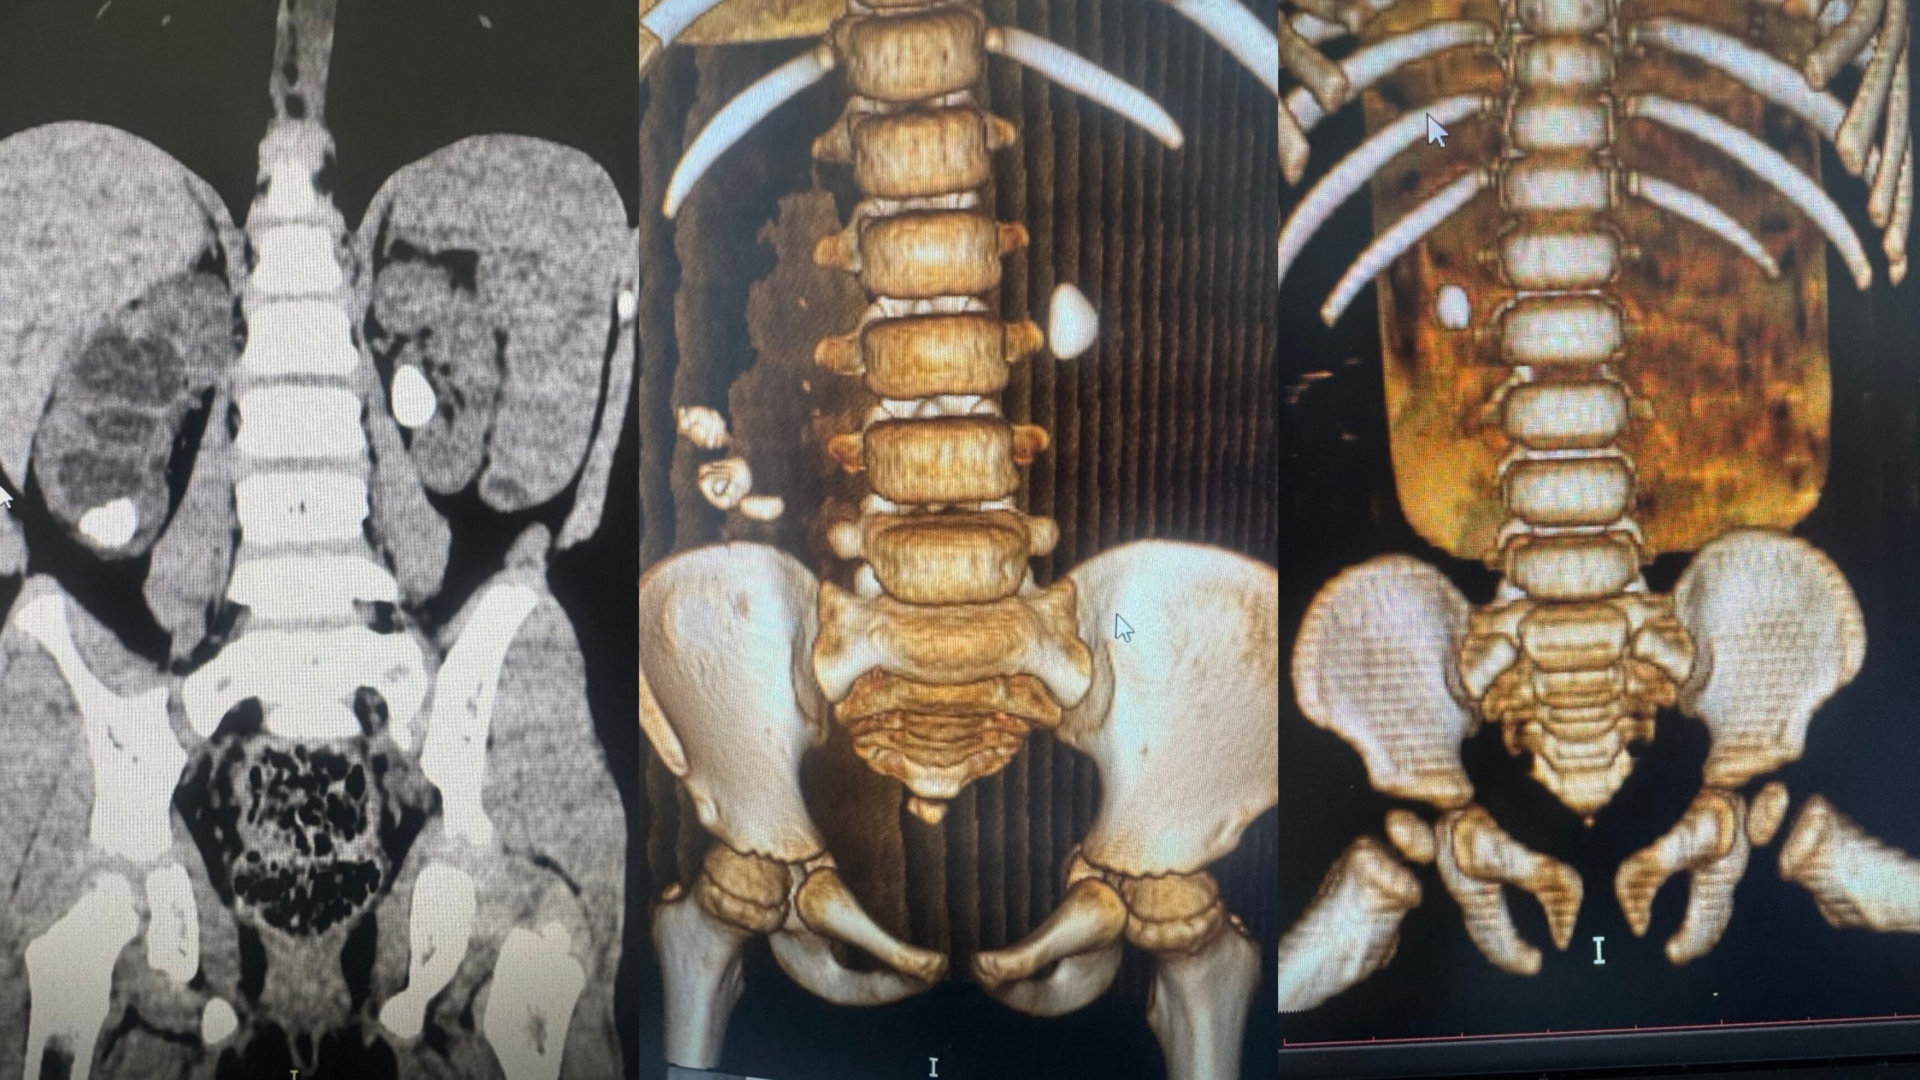

В среднем размер камней у детей составляет 5-7 миллиметров. Рекордным стал показатель — 6 сантиметров. Самым юным пациентом с диагнозом мочекаменная болезнь в 2025 году был малыш в возрасте 11 месяцев.